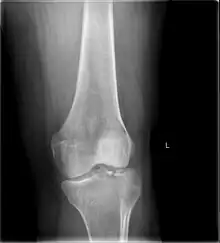

![]() | |

| A severe tibial plateau fracture with an associated fibular head fracture | |